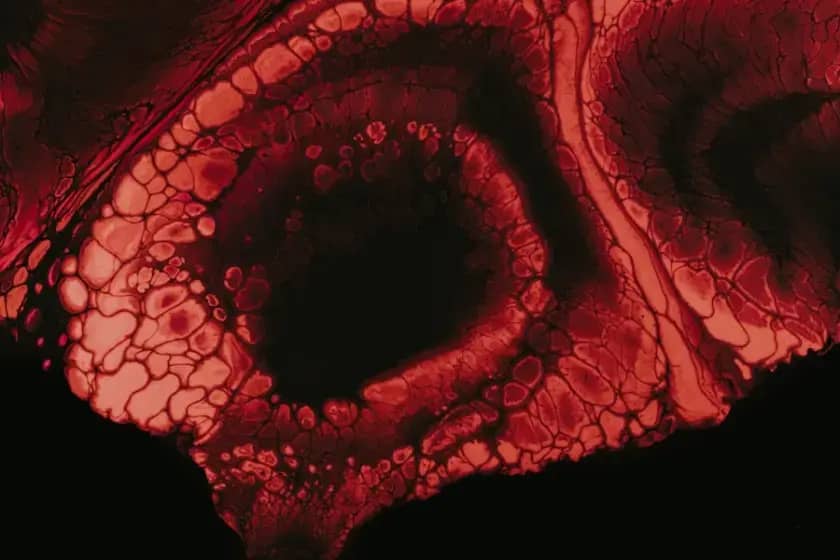

Portalna vena je glavni krvni sud portalnog venskog sistema koji prenosi krv iz želuca, tankog i debelog crijeva, slezine, pankreasa i žučne kesice prema jetri. Portalna vena donosi krv bogatu hranljivim materijama i toksinima koje jetra prerađuje prije nego što krv nastavi ka srcu.

Portalna vena i portalni venski sistem ključni su za filtraciju i metabolizam nutrijenata u jetri. Ako portalna vena ne funkcioniše pravilno, to može dovesti do poremećaja rada jetre i ozbiljnih posledica poput portalne hipertenzije ili tromboze.

Glavne pritoke portalne vene su gornja mezenterična vena, splenična vena, donja mezenterična vena, gastrične vene i cistične vene. Portalna vena se formira kod vrata pankreasa spajanjem gornje mezenterične i splenične vene i potom se razdvaja na grane koje snabdevaju različite djelove jetre.